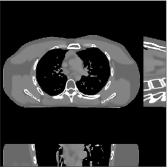

III-B3 Generalization Capability Comparisons between a “Denoising” Deep NN and the Proposed PWLS-ST- Method

This section compares the generalization capabilities between the proposed MBIR method, PWLS-ST-, and a denoising deep NN, FBPConvNet [14], that are trained from the phantom data; in particular, we tested the trained PWLS-ST- and FBPConvNet models to phantom and clinical scan data. The results in Fig. 6 show that the non-MBIR FBPConvNet method has higher overfitting risks, compared to the proposed PWLS-ST- MBIR method. When tested on clinical scan data, PWLS-ST- achieves much more accurate reconstruction, compared to FBPConvNet. See Fig. 6(b). When tested on phantom data, FBPConvNet generates more unnatural features as the number of views reduces, although it gives lower RMSE values compared to PWLS-ST-. See zoom-ins in Fig. 6(a). The FBPConvNet results above correspond to those in the recent work [16] that FBPConvNet [14] generated some unexpected structures.